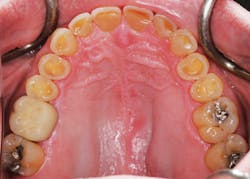

Figure 4: Erosion suggestive of untreated acid reflux or bulimia.

Tooth wear is a process resulting from three primary factors-abrasion (from the interaction of teeth with other materials); attrition (from tooth-to-tooth contact); and erosion (wear after teeth come into contact with environmental or dietary acids) (see Figures 2-5). In addition, numerous behaviors and health factors contribute to the process of tooth wear, including, but not limited to: a diet high in acidic beverages and foods, bruxism, aggressive or improper tooth brushing, low pH of the oral cavity (acid reflux, GI disorders, bulimia nervosa) and oral hygiene habits.

In one published survey of 100 consecutive cases of problematic tooth wear referrals, detailed histories were taken of each case to determine the etiology of tooth wear. Fifty-eight percent of cases were attributed to erosion alone or erosion combined with another etiology.

No cases could be attributed to abrasion alone.9